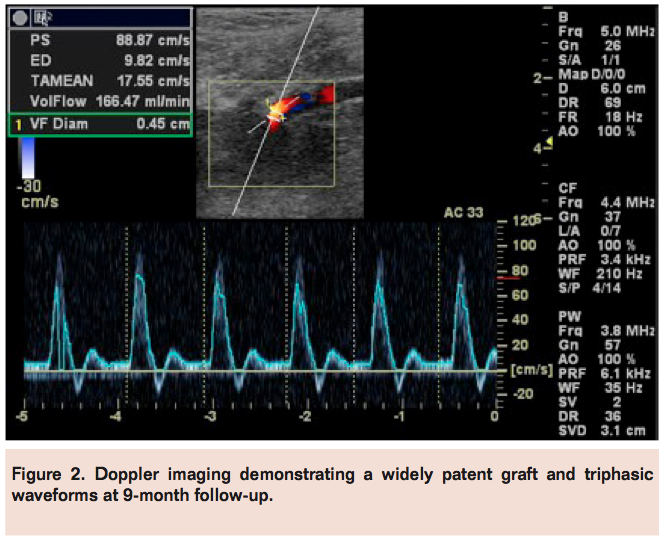

At 9-month follow-up, both feet were well perfused with palpable pedal pulses. The graft remained widely patent with normal flow and no evidence of graft stenosis (Figure 2). The ABI on the right lower extremity was 1.24, and on the left was 1.33.